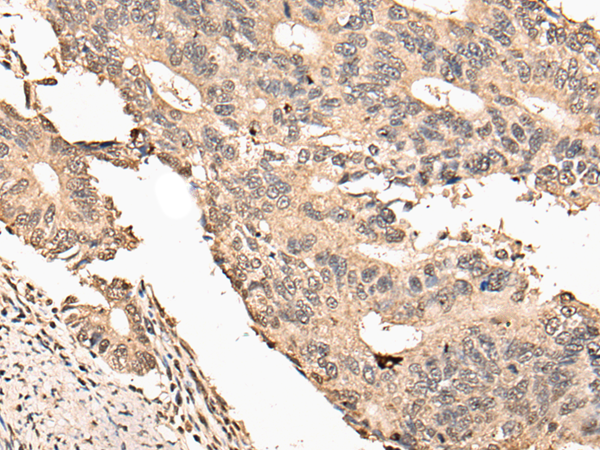

分类: 科研抗体货号: P09304别名: CIR1; UEV1; CROC1; UBE2V; UEV-1; UEV1A; CROC-1应用: WB,IHC反应种属: Human, Mouse